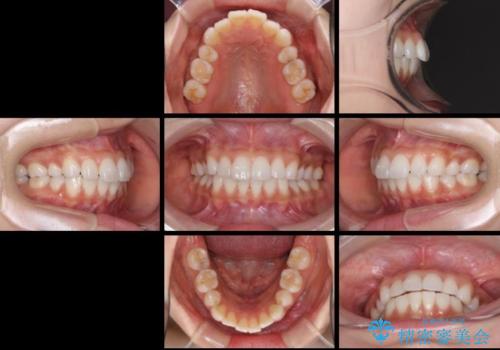

矯正治療の後戻り インビザラインによる再矯正治療

- 以前ワイヤー装置にて行った抜歯矯正の後戻りを気にして来院された患者様です。

前歯のデコボコにより、やや口元が突出した印象となっていたため、口元も引っ込めることとしました。

上下顎前歯に積極的にIPR(歯と歯の間を削る)を行い、インビザラインを用いて治療していくこととしました。

デコボコが解消されるのはもちろんのこと、突出感のあった前歯を引っ込めることができ、患者様には大変満足していただきました。